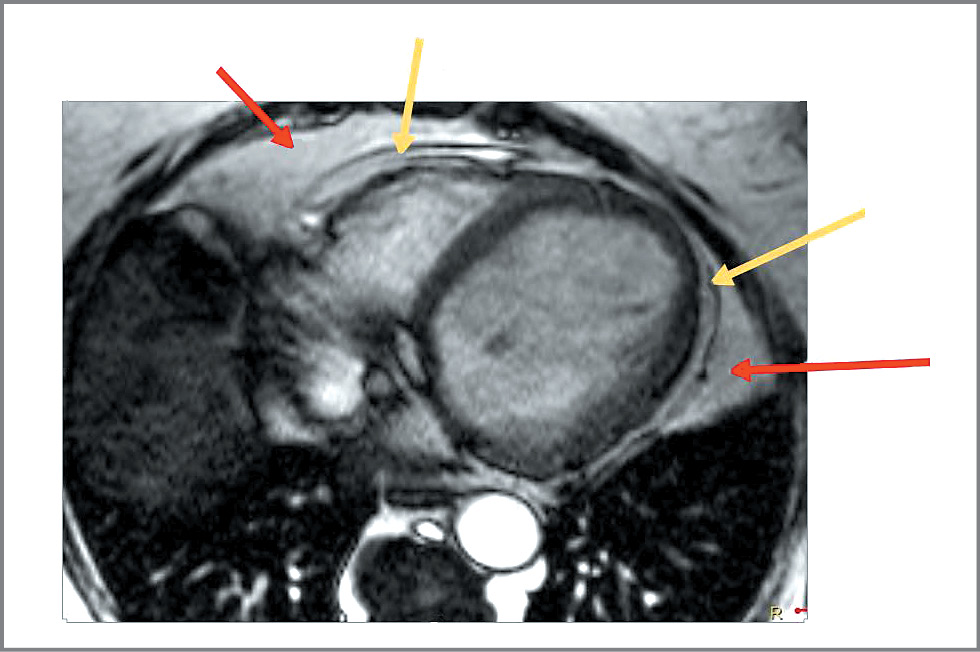

По данным лабораторных исследований обращает на себя внимание неадекватный контроль глюкозы: глюкоза крови 10,22 ммоль/л (при принятой в лаборатории норме 5,80 ммоль/л). Показатели липидного профиля на терапии аторвастатином 20 мг: общий холестерин – 4,5 ммоль/л, триглицериды – 3,48 ммоль/л, холестерин липопротеинов низкой плотности – 1,91 ммоль/л, холестерин липопротеинов высокой плотности – 1,01 ммоль/л. Уровень содержания трансаминаз в крови в пределах нормы, аспартатаминотрансфераза – 17,0 Ед/л; аланинаминотрансфераза – 20,0 Ед/л (при норме, принятой в лаборатории, 29 Ед/л). Нормальные показатели в крови уровня гормонов щитовидной железы исключили гипотиреоз как причину увеличения массы тела. На электрокардиограмме зарегистрирован синусовый ритм с частотой сердечных сокращений – 70 уд/мин, полная БЛНПГ. Эхокардиографическое исследование проведено на ультразвуковой системе экспертного класса VividE 9 с использованием фазированного датчика М5Sc-D и матричного датчика 4V-D (трехмерный режим); выполнена тканевая допплерография сердца для комплексной оценки диастолической функции желудочков (включая показатели Е/А, Е/Е`, Eml, Ems, Et). Фракция выброса и объемы ЛЖ рассчитывали биплановым методом дисков (модифицированный метод Симпсона в В-режиме). Размеры и объемы полостей сердца индексировали на площадь поверхности тела и соотносили с нормативными значениями. По данным ЭхоКГ, на фоне полной БЛНПГ определялось расширение ЛП и ЛЖ: ПЗР ЛП – 4,6 см (норма 2,7–3,8 см), апикально 5,4×4,7 см (норма 5,3×4,0 см); объем ЛП – 80 мл (норма до 52 мл); индекс объема ЛП 37,6 мл/м2 (норма до 34 мл/м2); конечно-диастолический размер ЛЖ в базальных отделах – 6,3 см (норма 3,8–5,2 см), в средних отделах – 7,9 см; конечно-систолический размер ЛЖ – 6,7 см (норма 2,2–3,5 см). Правое предсердие визуально не расширено, правый желудочек не расширен: ПЗР 2,7 см (норма до 2,9 см). Сократительная функция миокарда ЛЖ снижена: фракция выброса – 35%. Стенки ЛЖ умеренно утолщены: толщина межжелудочковой перегородки – 1,1 см; толщина задней стенки ЛЖ – 1,1 см (норма 0,6–0,9 см). Масса миокарда ЛЖ увеличена – 477,7 г (норма до 162 г); индекс массы миокарда ЛЖ увеличен – 224,3 г/м2 (норма до 95 г/м2). Умеренное повышение систолического давления в легочной артерии до 35 мм рт. ст. (норма до 30 мм рт. ст.). Скорость и время трансмитрального потока свидетельствуют о замедленной релаксации. Асинхронно движется переднеперегородочная область, очевидно, из-за наличия БЛНПГ. На фоне БЛНПГ не удается выявить четкую зону нарушения сократимости миокарда ЛЖ. Общая сократимость миокарда ЛЖ снижена. Нарушена диастолическая функция миокарда ЛЖ. По данным магнитно-резонансной томографии (МРТ) с контрастным усилением, на фоне внутривенного введения гадолиния выявлено расширение камер ЛЖ (конечно-диастолический размер ЛЖ составил 6,1–6,3 см), асинхронное сокращение миокарда межжелудочковой перегородки, по-видимому, за счет БЛНПГ. Нарушений сегментарной сократимости миокарда ЛЖ не выявлено. Очагового поражения миокарда желудочков ишемического или воспалительного генеза не выявлено. ПЗР ЛП составил – 4,1 см, толщина межжелудочковой перегородки – 1,1 см, толщина задней стенки ЛЖ – 0,9 см. Также выявлены липоматоз межпредсердной перегородки (МПП), скопление избыточного количества жировой ткани в полости перикарда вдоль свободной стенки правого желудочка, верхушки сердца и правой атриовентрикулярной борозды толщиной до 12 мм. Объем перикардиального жира составил 187 см3, в том числе в области МПП – 30,1 см3 (рис. 1, 2).

Рис. 2. МРТ сердца: кино-МРТ, 4-камерная длинная ось ЛЖ. Красная стрелка указывает на паракардиальный жир (внутригрудной), желтая – эпикардиальный жир, в том числе в проекции правой атриовентрикулярной борозды, МПП, задней стенки правого предсердия.

Fig. 2. Cardiac MRI: Cine- MRI, 4-chamber long axis of the left ventricle. The red arrow indicates paracardial fat (intrathoracic), the yellow arrow indicates epicardial fat, including in the projection of the right atrioventricular sulcus, intraatrial septum, and the right atrium posterior wall.